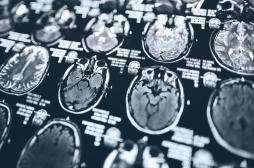

LES MALADIES